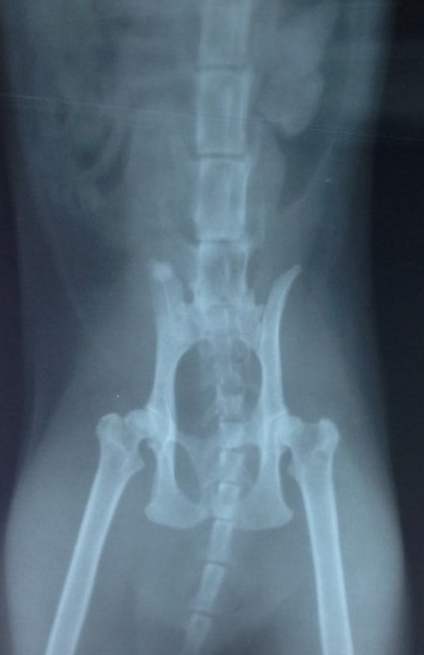

品种:加菲猫 名字:菲菲 年龄:三岁 性别:雄性

病史:一年前被现在的主人送人,送人半年后出现尿血,主人带到一个动物医院检查,当时未拍摄X光片 及B超检查,诊断为膀胱炎,打几天针有好转,但扔尿血,主人后来没有再带菲菲去医院继续治疗,只是在家饲养,菲菲在家饲养时常出现尿血、尿频、饮食饮水正常。

菲菲因为到处乱排尿,前几天收养人把菲菲还给了原来的主人,好心的主人发现此猫尿血赶紧带到我院来检查,根据菲菲的临床症状我们给它做了B超、X光、血常规检查、生化检查。